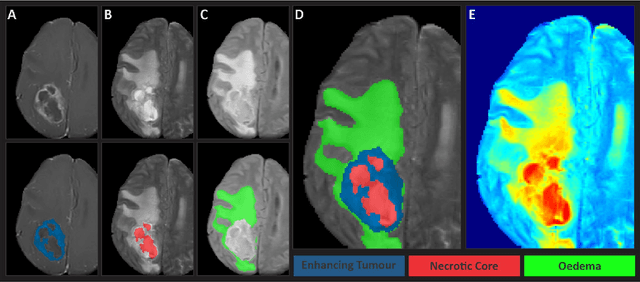

Abstract:Gliomas are the most common type of primary brain tumors. Although gliomas are relatively rare, they are among the deadliest types of cancer, with a survival rate of less than 2 years after diagnosis. Gliomas are challenging to diagnose, hard to treat and inherently resistant to conventional therapy. Years of extensive research to improve diagnosis and treatment of gliomas have decreased mortality rates across the Global North, while chances of survival among individuals in low- and middle-income countries (LMICs) remain unchanged and are significantly worse in Sub-Saharan Africa (SSA) populations. Long-term survival with glioma is associated with the identification of appropriate pathological features on brain MRI and confirmation by histopathology. Since 2012, the Brain Tumor Segmentation (BraTS) Challenge have evaluated state-of-the-art machine learning methods to detect, characterize, and classify gliomas. However, it is unclear if the state-of-the-art methods can be widely implemented in SSA given the extensive use of lower-quality MRI technology, which produces poor image contrast and resolution and more importantly, the propensity for late presentation of disease at advanced stages as well as the unique characteristics of gliomas in SSA (i.e., suspected higher rates of gliomatosis cerebri). Thus, the BraTS-Africa Challenge provides a unique opportunity to include brain MRI glioma cases from SSA in global efforts through the BraTS Challenge to develop and evaluate computer-aided-diagnostic (CAD) methods for the detection and characterization of glioma in resource-limited settings, where the potential for CAD tools to transform healthcare are more likely.